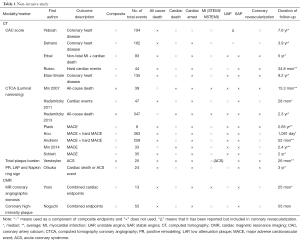

The common outcomes reported in the coronary atherosclerosis are summarized in Tables 1 and 2, which illustrate significant heterogeneity in the definition of outcomes, not only the variety in definitions of MACE but the inclusion or exclusion of all-cause mortality and unstable angina in various trials. There is also further fragmentation of definitions with some trials including only angina requiring hospitalization vs. requiring intervention vs. all angina. Clearly the presence of “stenosis >50%” on angiography does not carry the same weight as “cardiac death”. Given predictive value of a test is clearly influenced by the outcome measured it should serve as a caution pertaining to the subsequent discussion and indeed in any assessment of outcome measures.

The follow-up duration in a clinical study closely parallels the era when a modality becomes available for widespread-use. Table 1 clearly illustrates how CAC/CA score, CTCA, Plaque assessment and cMRA all have progressively lower/shorter durations of follow-up. As such any differences in event rates need to be interpreted in light of this follow-up period. From an invasive perspective, this difference is mirrored in the paucity of predictive supporting OCT compared to IVUS (Table 2).